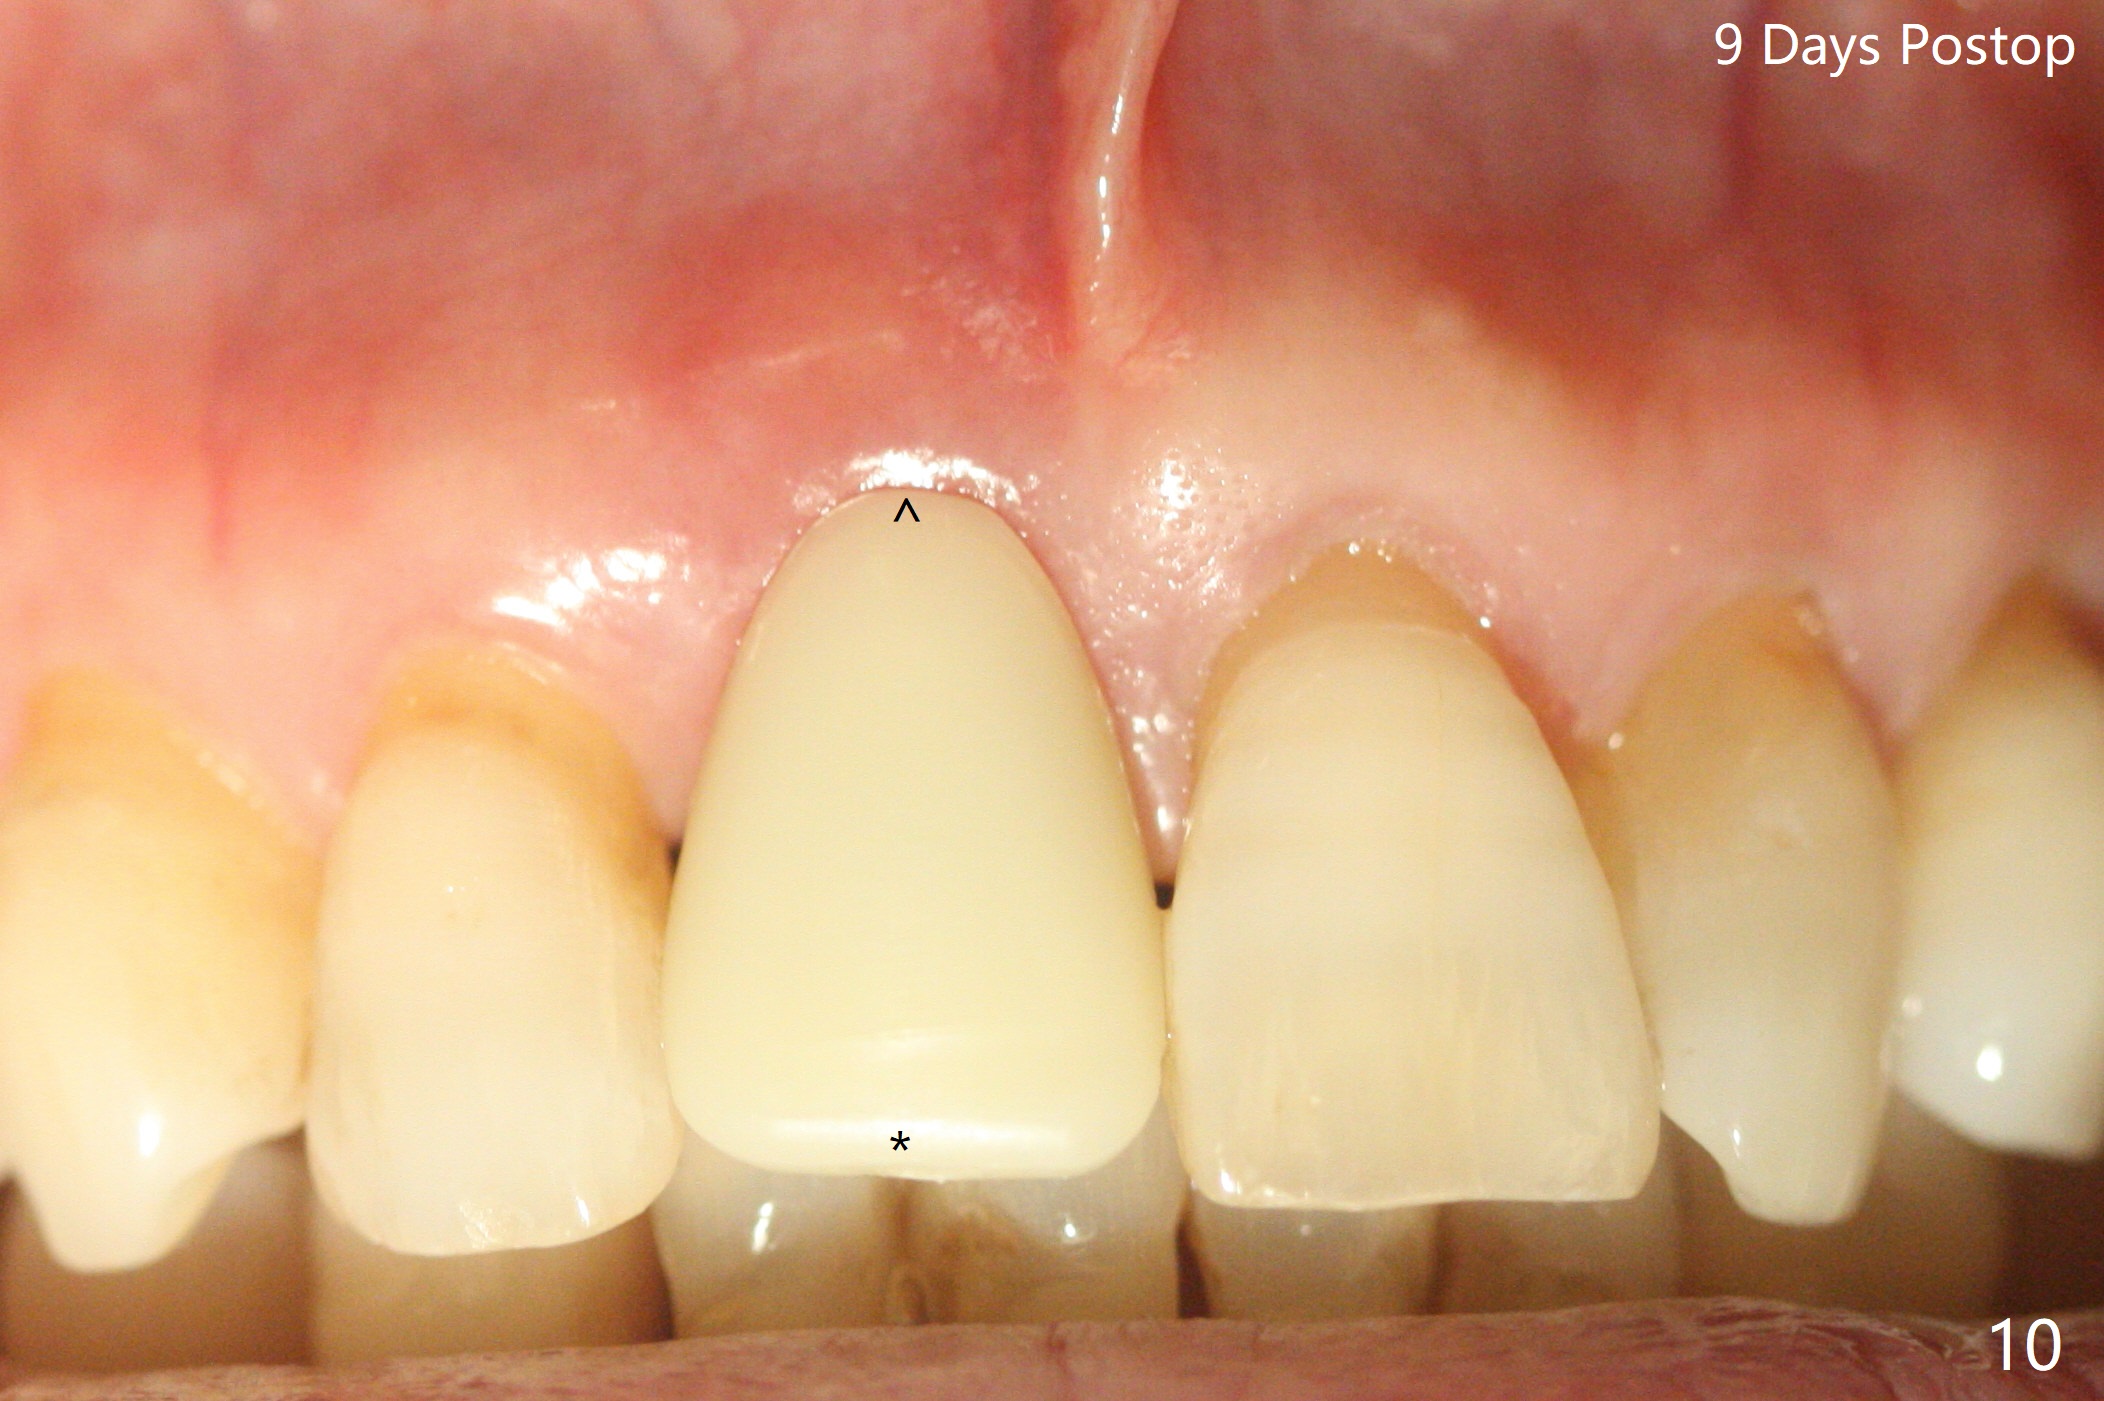

59岁女术前右下1,2切缘磨短后,右上1颊侧移位得到纠正(图一(咬合创伤))。拔牙后证实颊侧骨板缺失,钻洞始于腭侧(图二),当1.5毫米钻头感觉刚穿破鼻底时,置入2.5x14(4)毫米一段式植体,好像进入鼻腔,但是扭力<10Ncm(图三)。把一张PRF膜放入牙槽窝,一端紧贴颊侧牙龈腭侧,另一端放置颊侧牙龈颊侧(图四),然后开始用粘性骨粉(图五,七:*(100%皮质骨))充填颊侧间隙。后者填满时(图五:*),将外面一端PRF翻转覆盖牙槽窝开口,并插入基台固定(图六),最后插入龈下,用临时牙冠固定(图八(T),九(*:PRF))。术后九天牙龈退缩(图十:^),临时牙冠突出(*),后者龈缘和切缘进行调整,缩短(图十一,十二),少许骨粉暴露(图十二:>),十四天后牙龈往下生长,好像形成角化龈(图十三:*)。